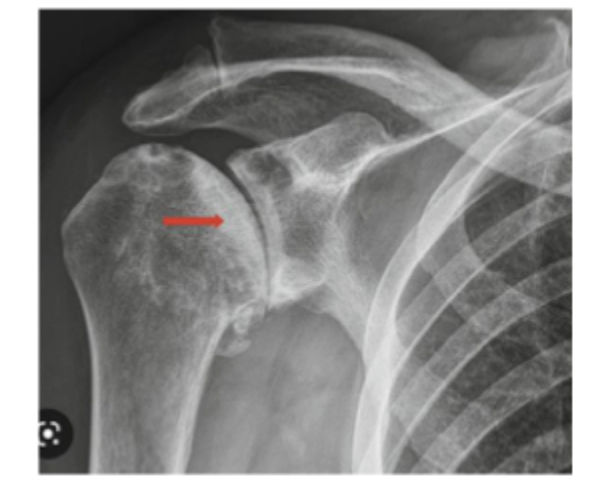

sclerosis in later stages → subchondral collapse

Signs of AVN on x-ray

normal xrays but MRI reveals death of the bone

Stage I of AVN is characterized by

Can be seen more on regular x-rays without collapse of the femoral head

Stage II of AVN is characterized by

xrays show signs of collapse “crescent signs”

Stage III of AVN is characterized by

x-ray has collapse and signs of cartilage damage (arthritis)

Stage IV of AVN is characterized by